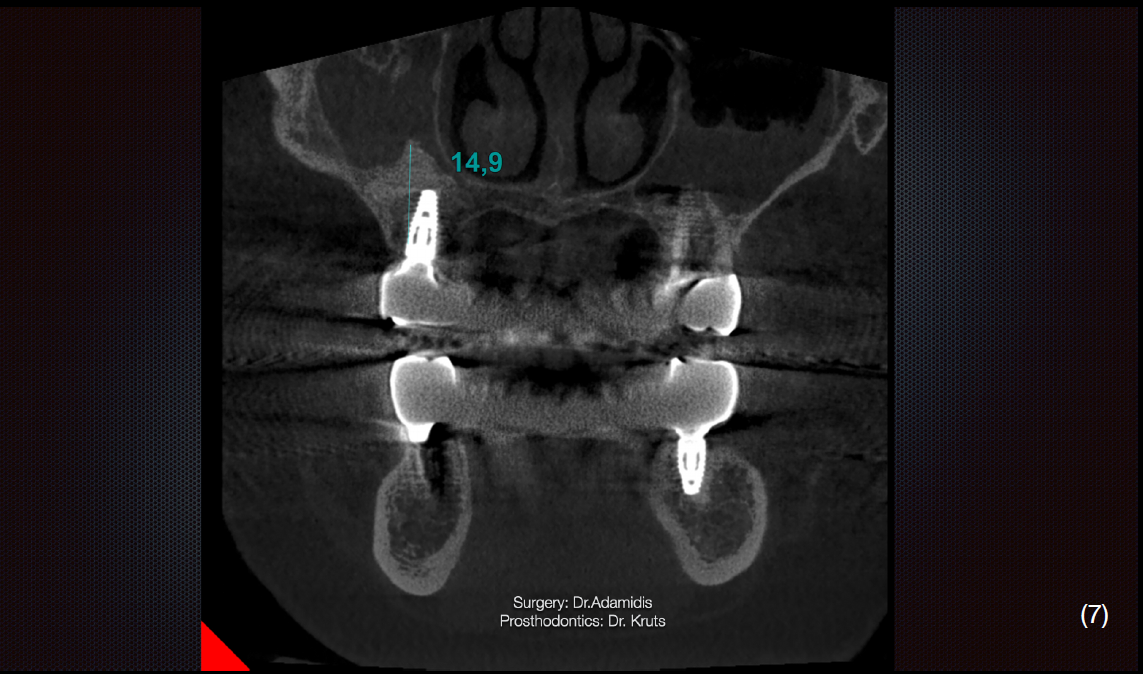

Також було звернено увагу на недостатню вертикальну кісткову пропозицію в дистальних відділах 1 та 2 квадрантів. Зуби нижньої щелепи було заплановано видалити з огляду на недостатню кісткову підтримку та неможливість протезування.

Через 3 місяці після першого етапу було проведено операцію на верхній щелепі. Було виконано відкритий синус-ліфтинг в першому квадранті та закритого в другому.

Матеріалом, що використовувався під час операції був Straumann Xenograft та аутологічна кістка, яка була забрана із ділянки зовнішньої косої лінії.

Одномоментно з кістковою аугментацією встановлено імплантати Strauman BLT діаметром 3.3mm в ділянках 12, 15, 17, 23, 25 зубів. Операційну рану було ушито, зворотньо зафіксовано тимчасову конструкцію на наявних зубах.